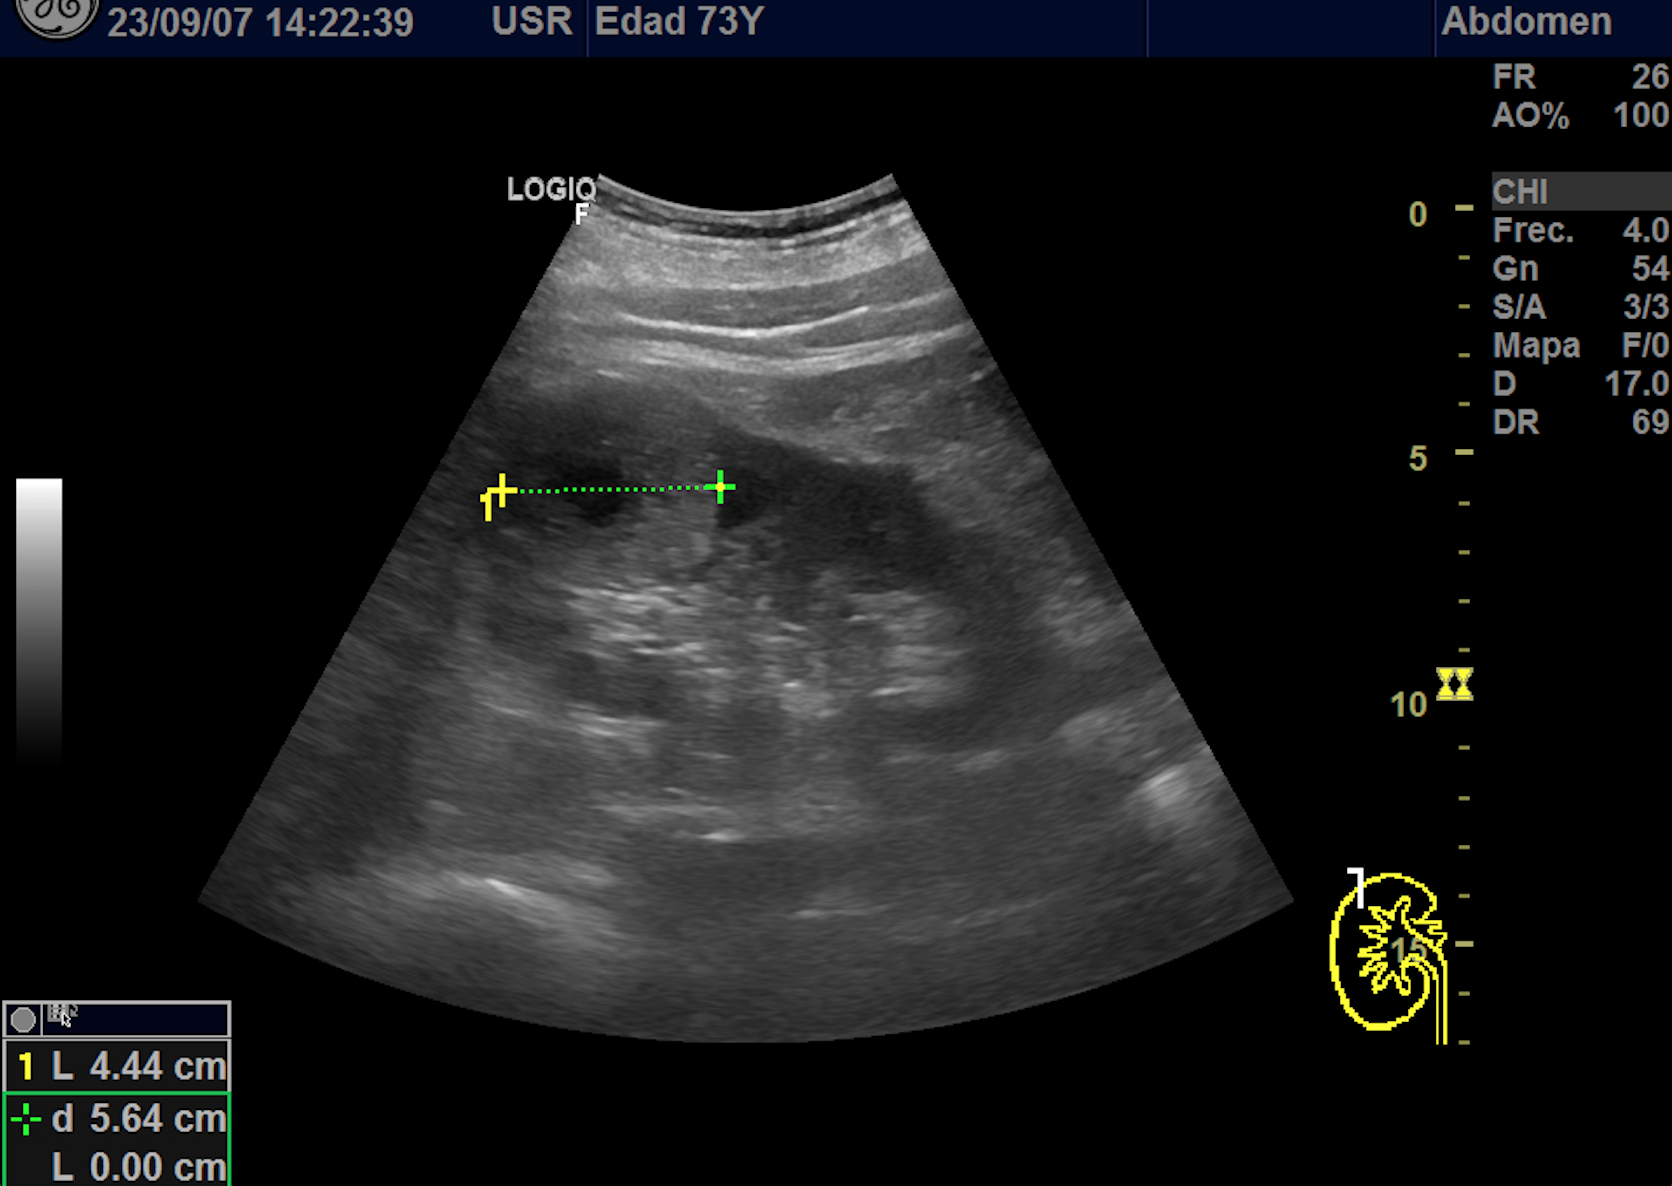

Hallazgos ecográficos

En polo superior de riñón derecho se observa una imagen redondeada, bien delimitada, isoecoica con un área central hipoecoica con vascularización periférica y central de 4,1 x 4,18 x 4,94 cm.

Riñon izquierdo sin hallazgos.